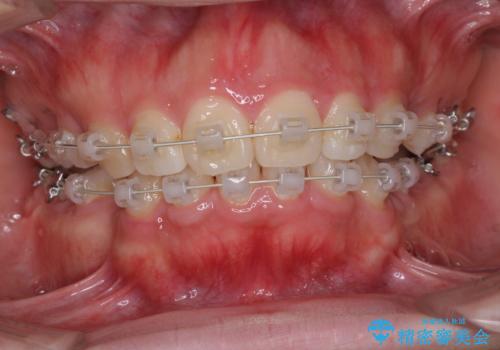

がたがたと出っ歯を直したい ワイヤーによる抜歯矯正

- ガタガタと出っ歯を主訴に来院されました。

上下左右の歯を1本ずつ、合計4本抜歯してワイヤーにて矯正治療をすることとなりました。

前から4番目の歯を抜歯することが多いのですが、右上の前から5番目の歯が神経の治療済みであり、こちらの歯を抜歯する計画としました。

通常より治療期間を要しましたが、健康な歯を残すことができました。